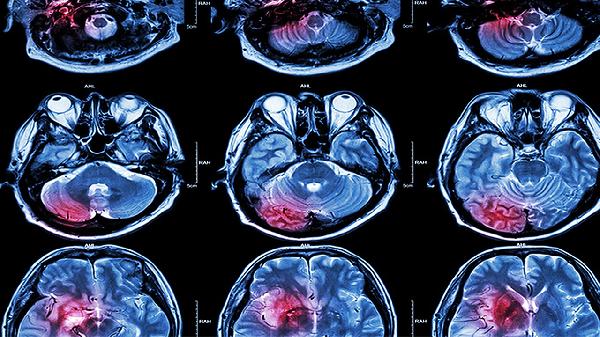

脑溢血手术后再次出血可能与术后血压控制不佳、血管异常、凝血功能障碍、手术操作因素或术后感染等因素有关。脑溢血是指非外伤性脑实质内血管破裂引起的出血,术后再出血是严重并发症,需立即就医处理。

血肿清除过程中电凝不充分、止血材料覆盖不全可能导致术区再出血。术中脑组织牵拉过度也可能损伤周围血管。术后24-48小时内CT显示原术区出现新月形高密度影提示活动性出血。这种情况需紧急二次手术探查,使用吸收性明胶海绵、纤维蛋白胶等加强止血。